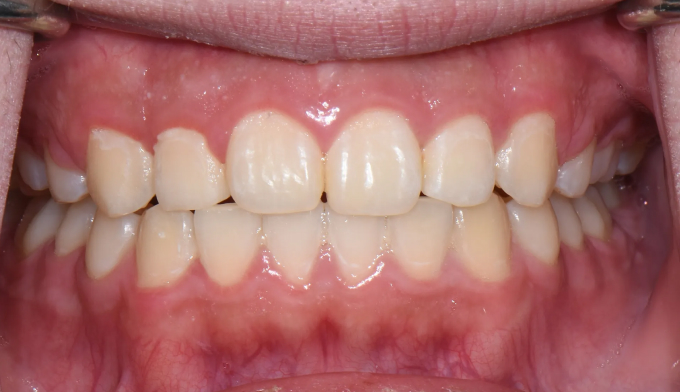

돌출입을 해소하고 동시에 가지런하지 못한 치열을 바르게 펴서 양치하기 좋은 상태로 만들어줍니다.

총 교정기간은 23개월입니다.